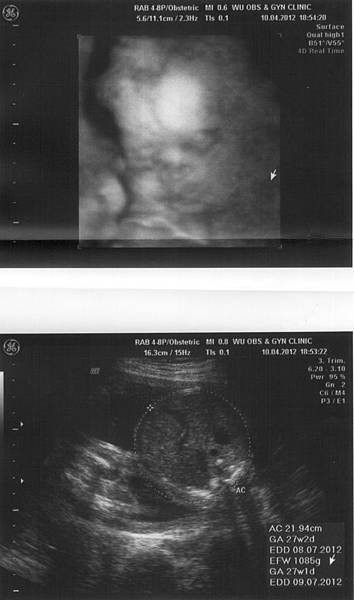

登登~這次產檢,小Bella的體重已經有785g,

醫生說"好像"有點大,但都在正常值裡,